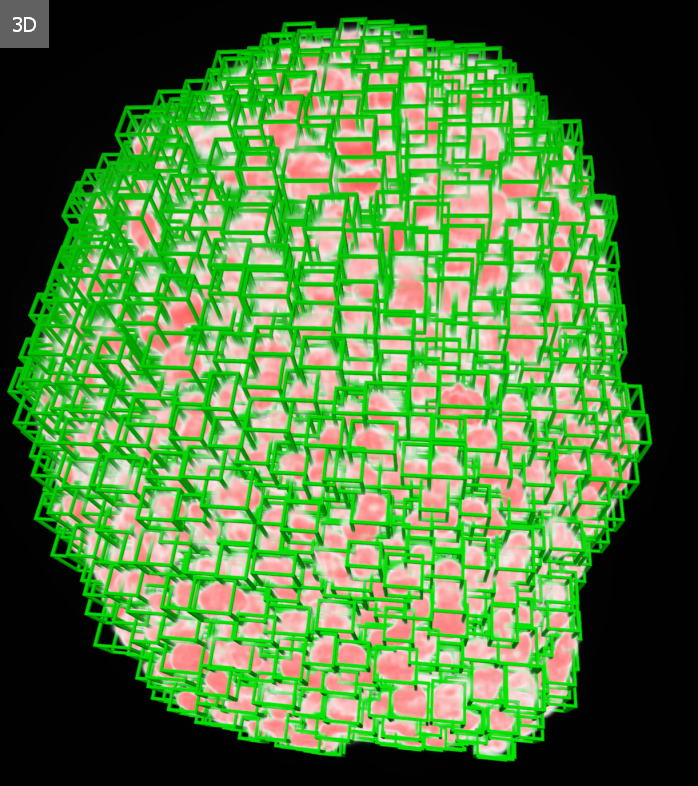

Eddig is léteztek 3D-s szövetmodellek, az úgynevezett szferoidok, és létezett a light-sheet mikroszkópia is, amellyel rétegről rétegre láthatóvá tehetők ezek a miniatűr emberi minták.

A Nature Communications-ben megjelent tanulmány szerint a HCS-3DX új korszakot nyithat a háromdimenziós sejtvizsgálatokban, mert először teszi lehetővé a sejtek térbeli viselkedésének kvantitatív, egysejt-szintű elemzését, ami kulcsfontosságú a gyógyszerek hatásmechanizmusainak megértésében.

A Nature Communications-ben megjelent publikáció szerint a HCS-3DX integrált módon fogja össze a 3D-s sejtkultúrák vizsgálatának minden lépését – az automatizált mintakezeléstől a light-sheet mikroszkópos képalkotáson át az egysejt-analízisig.

A kutatók azt is kimutatták, hogy az új mintatartó kétszer gyorsabb szkennelést biztosít, mint a hagyományos agarózos eljárások, miközben a képminőség változatlanul kiváló marad.